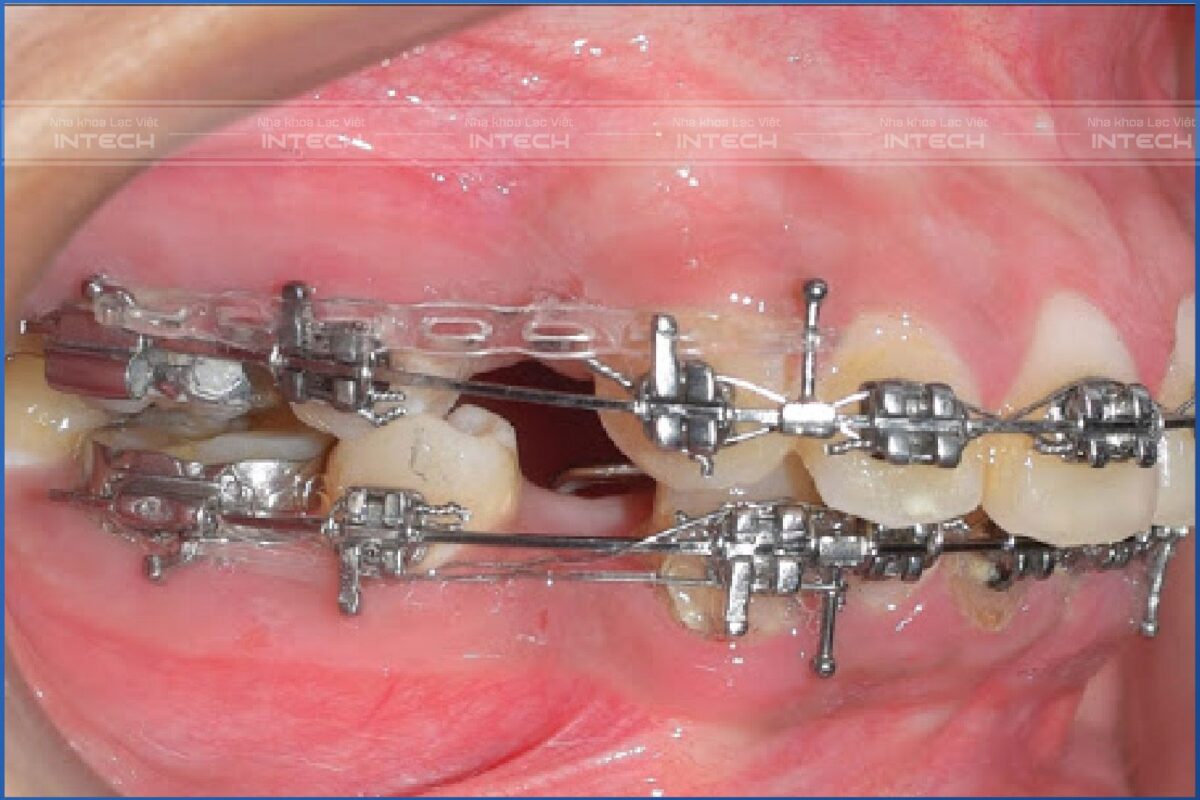

Trong niềng răng, có một tỉ lệ lớn các trường hợp được chỉ định nhổ bỏ răng hàm nhỏ thứ nhất (răng số 4) để giải quyết vấn đề chen chúc hoặc giảm hô. Nhổ răng số 4 thường tạo ra khoảng trống 7-8mm, vì vậy mất khoảng từ 7-16 tháng cho giai đoạn đóng khoảng.

Thời gian đóng khoảng mất khoảng từ 7 đến 16 tháng

Tương tự, một số trường hợp phải nhổ bỏ răng khác, ví dụ như răng hàm lớn thứ nhất (răng số 6) bị bệnh lý, khoảng trống tạo ra là 10-12mm. Vậy nên thời gian kéo khít khoảng phải dài hơn.

Khí cụ niềng răng chất lượng tốt